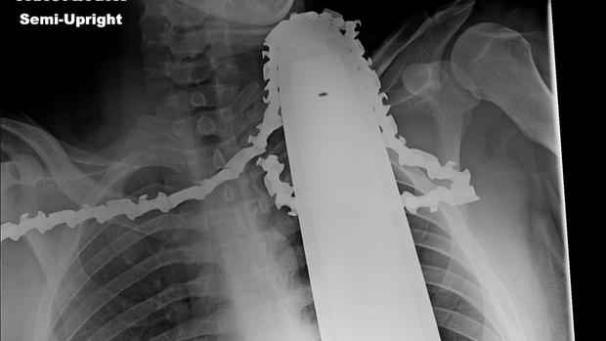

Man komt ziekenhuis binnen met kettingzaag in zijn nek